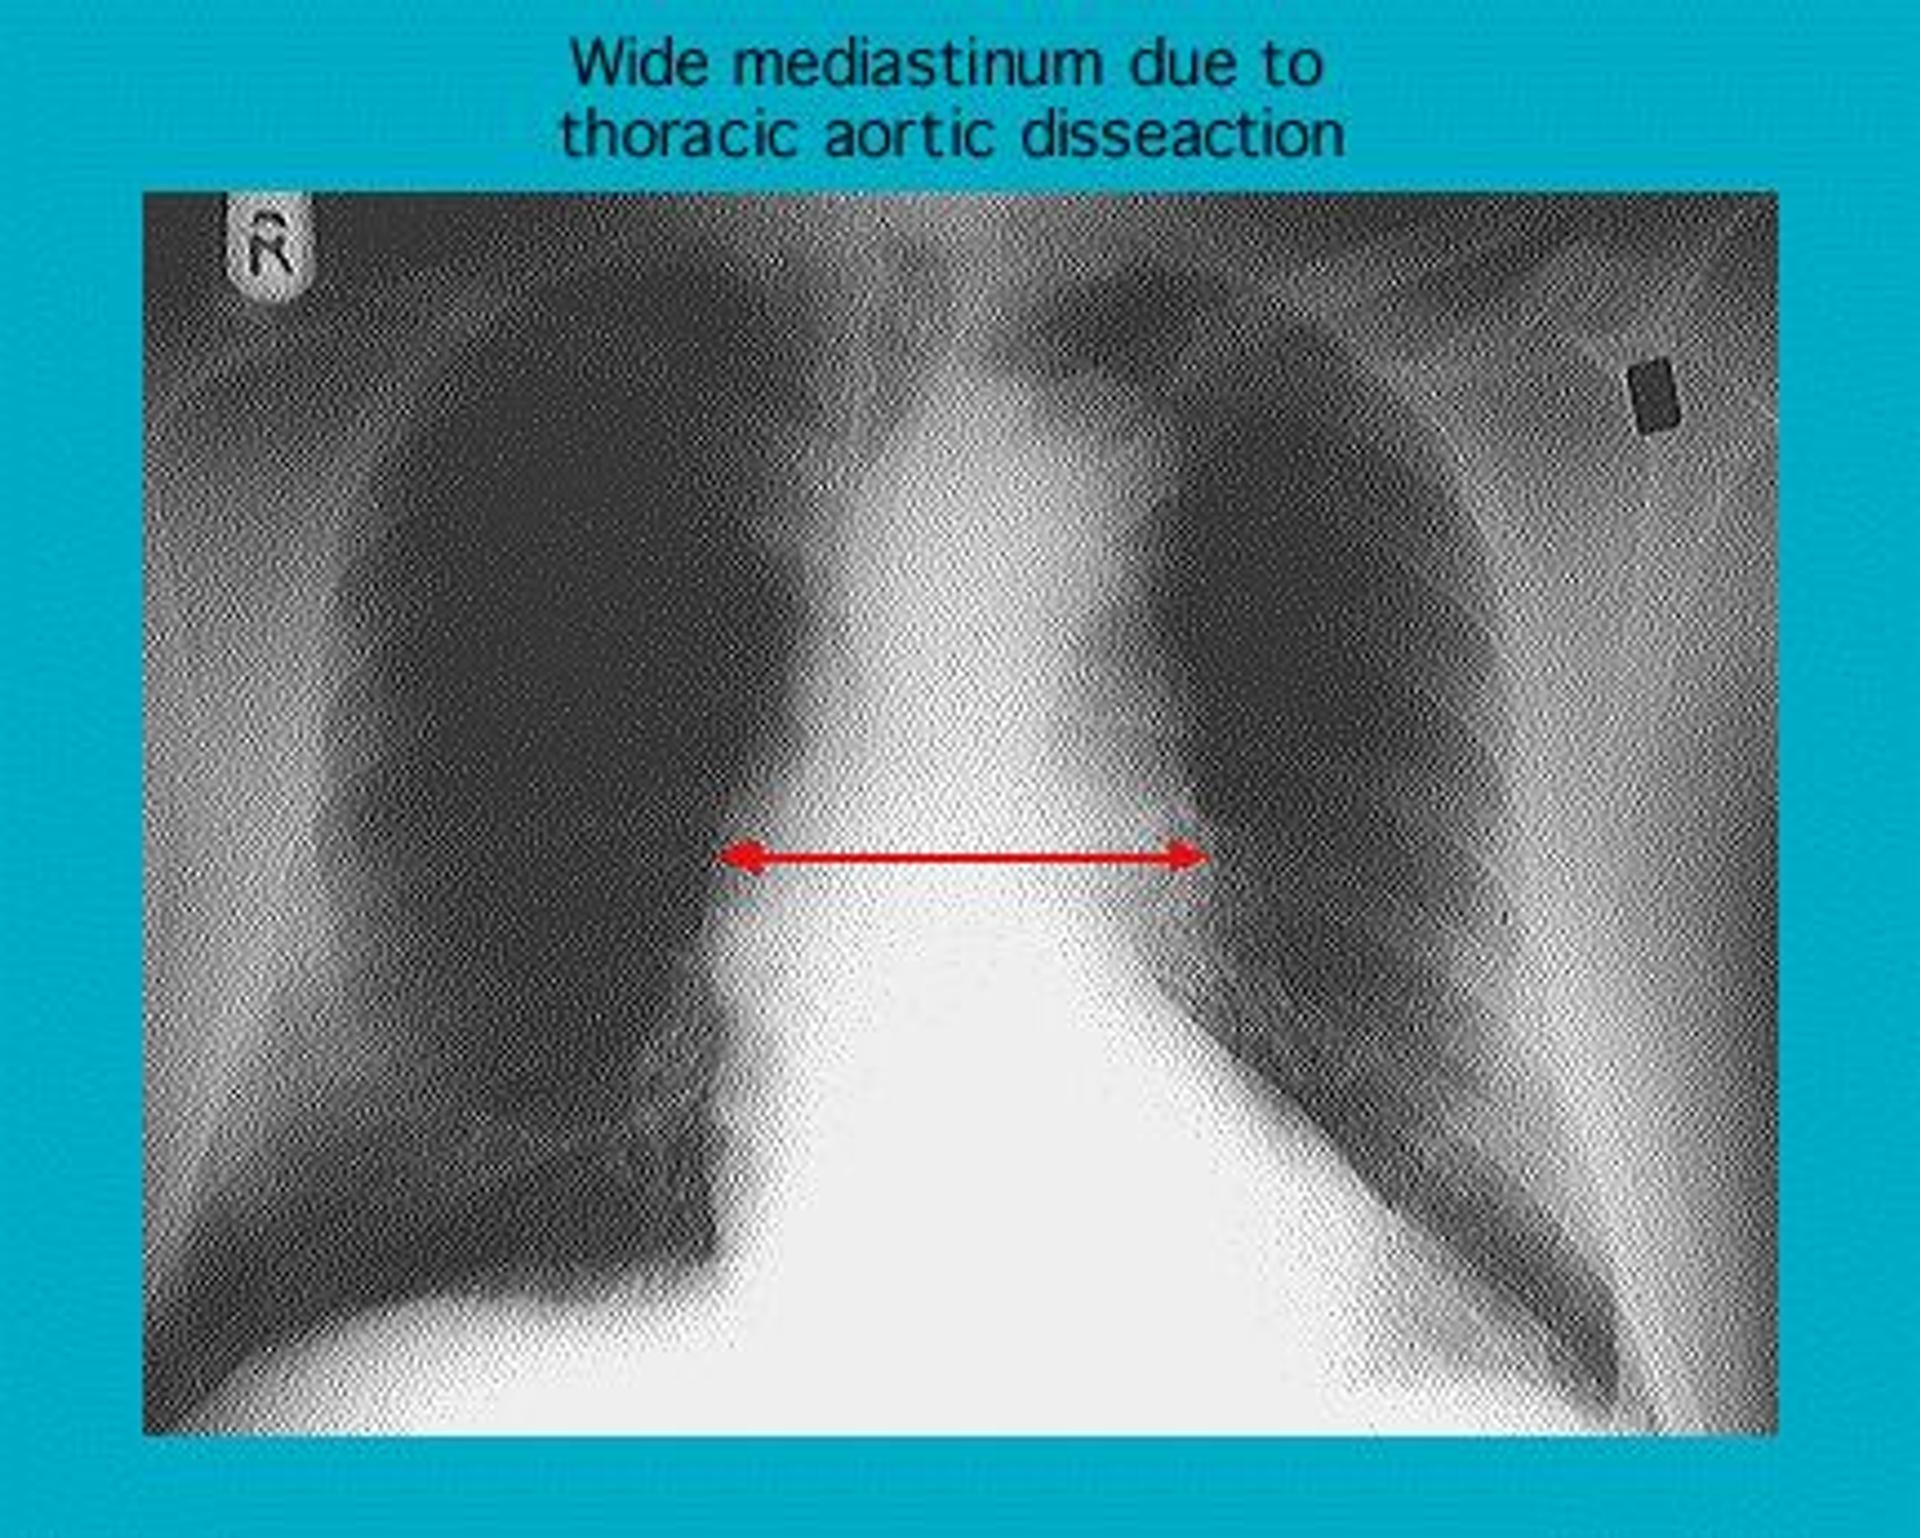

Radiograph showing dissection of the thoracic aorta